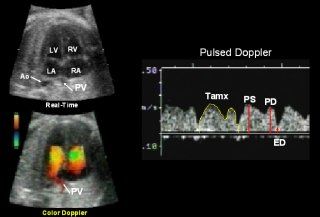

It has been estimated that between 17% and 31% of the total cardiac output crosses the foramen ovale 18. Although real-time ultrasound is used to image this structure, color Doppler ultrasound allows the examiner to identify the direction of the blood flowing through the foramen ovale so that the pulsed Doppler sample volume can be properly placed to record the waveform 19. As the result of low-velocity flow through the foramen ovale, the color Doppler velocity setting should be decreased to a level less than that used for imaging the ventricular chambers and the outflow tracts. The pulsed Doppler waveform is obtained by placing the Doppler sample volume lateral to the atrial septum, within the foramen ovale

The color Doppler ultrasound identification of the pulmonary veins entering the left atrium was first reported by DeVore in 1992 22. Using a similar technique, Laudy and colleagues in 1995 identified pulmonary veins entering the left atrial chamber and recorded the venous waveform with pulsed Doppler ultrasound23 . They identified three pulsatile forward flow components (ventricular systole, early ventricular diastole, and atrial systole) in the normal waveform which occur during the cardiac cycle

Pulmonary Vein

In 1995 Laudy and colleagues measured the peak velocity of the S, D, and A waves and computed the S/A ratio 23. They also measured the Tamx for the entire waveform. They found a significant increase of the Tamx, and the S, D, and A peak velocity waveforms with advancing gestational age. The S/D ratio demonstrated a statistically significant decrease with advancing gestational age. 23.